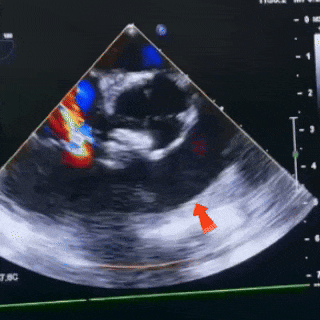

4.室间隔室上嵴回声连续中断。CDFI:室水平见收缩期高速左至右过隔分流信号,束宽约2.9mm,CW:4.21m/s ,PG:71mmHg。

缺损情况:室间隔室上嵴回声连续中断,室水平见收缩期高速左至右过隔分流信号,束宽约2.9mm。

锁定前观察

双盘展开后,封堵器骑跨于室间隔

彩色血流显示无残余分流